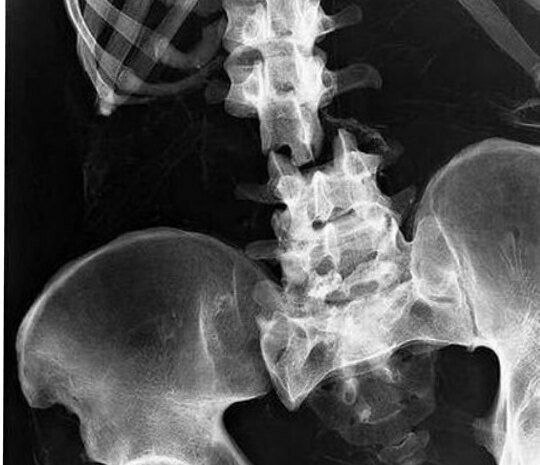

Перелом позвоночника: последствия и важные аспекты

Перелом позвоночника — серьезная травма, которая может привести к различным осложнениям, включая нарушение мочеиспускания и дефекации. Это происходит из-за повреждения спинного мозга или нервных корешков, которые отвечают за контроль над функциями мочевого пузыря и кишечника.